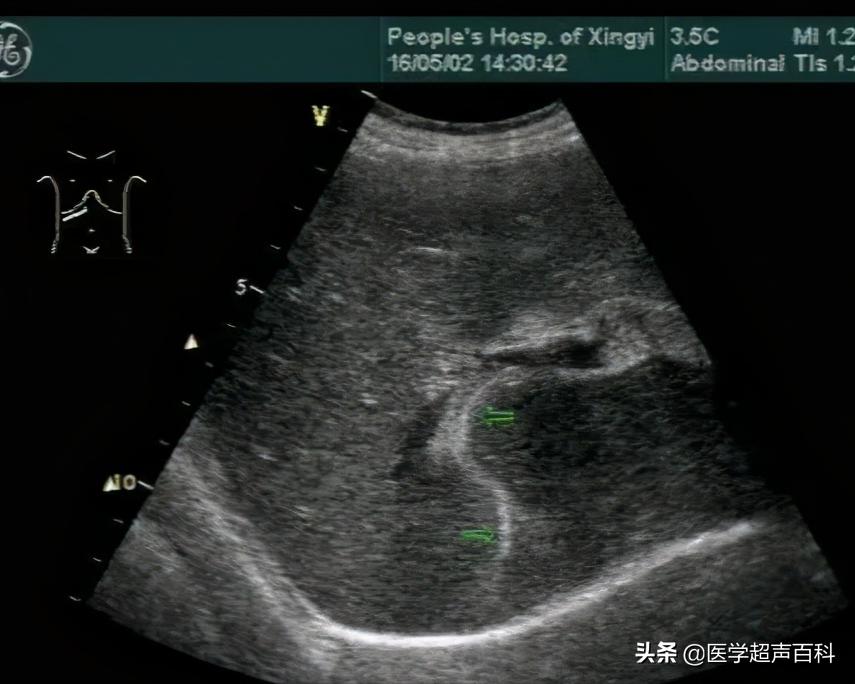

1.肝外胆管呈不同程度的扩张,胆总管常呈明显扩张。

2.扩张的胆管内有数毫米宽的平行双线状的高回声带,前端圆钝,形态自然、边缘清晰、光滑。光带间暗区是蛔虫的假体腔,其内可见间断的点线状高回声。蛔虫死后,其中心暗带逐渐变得模糊甚至消失。

3.有多条蛔虫胆管内可见多条双线状平行高回声带,如几十条蛔虫绞成团,堵塞胆管时见到胆管有极度扩张。

4.实时超声探测看到虫体在胆管内蠕动是具有诊断意义的特异性表现。

超声显像诊断胆道蛔虫病是简便、实用而有效的方法,其准确率高达百分之九十五以上,如胆管扩张,胆汁充盈,可见到特征性双线状高回声带可作本病诊断的依据,如显示活蛔虫蠕动即可确诊。